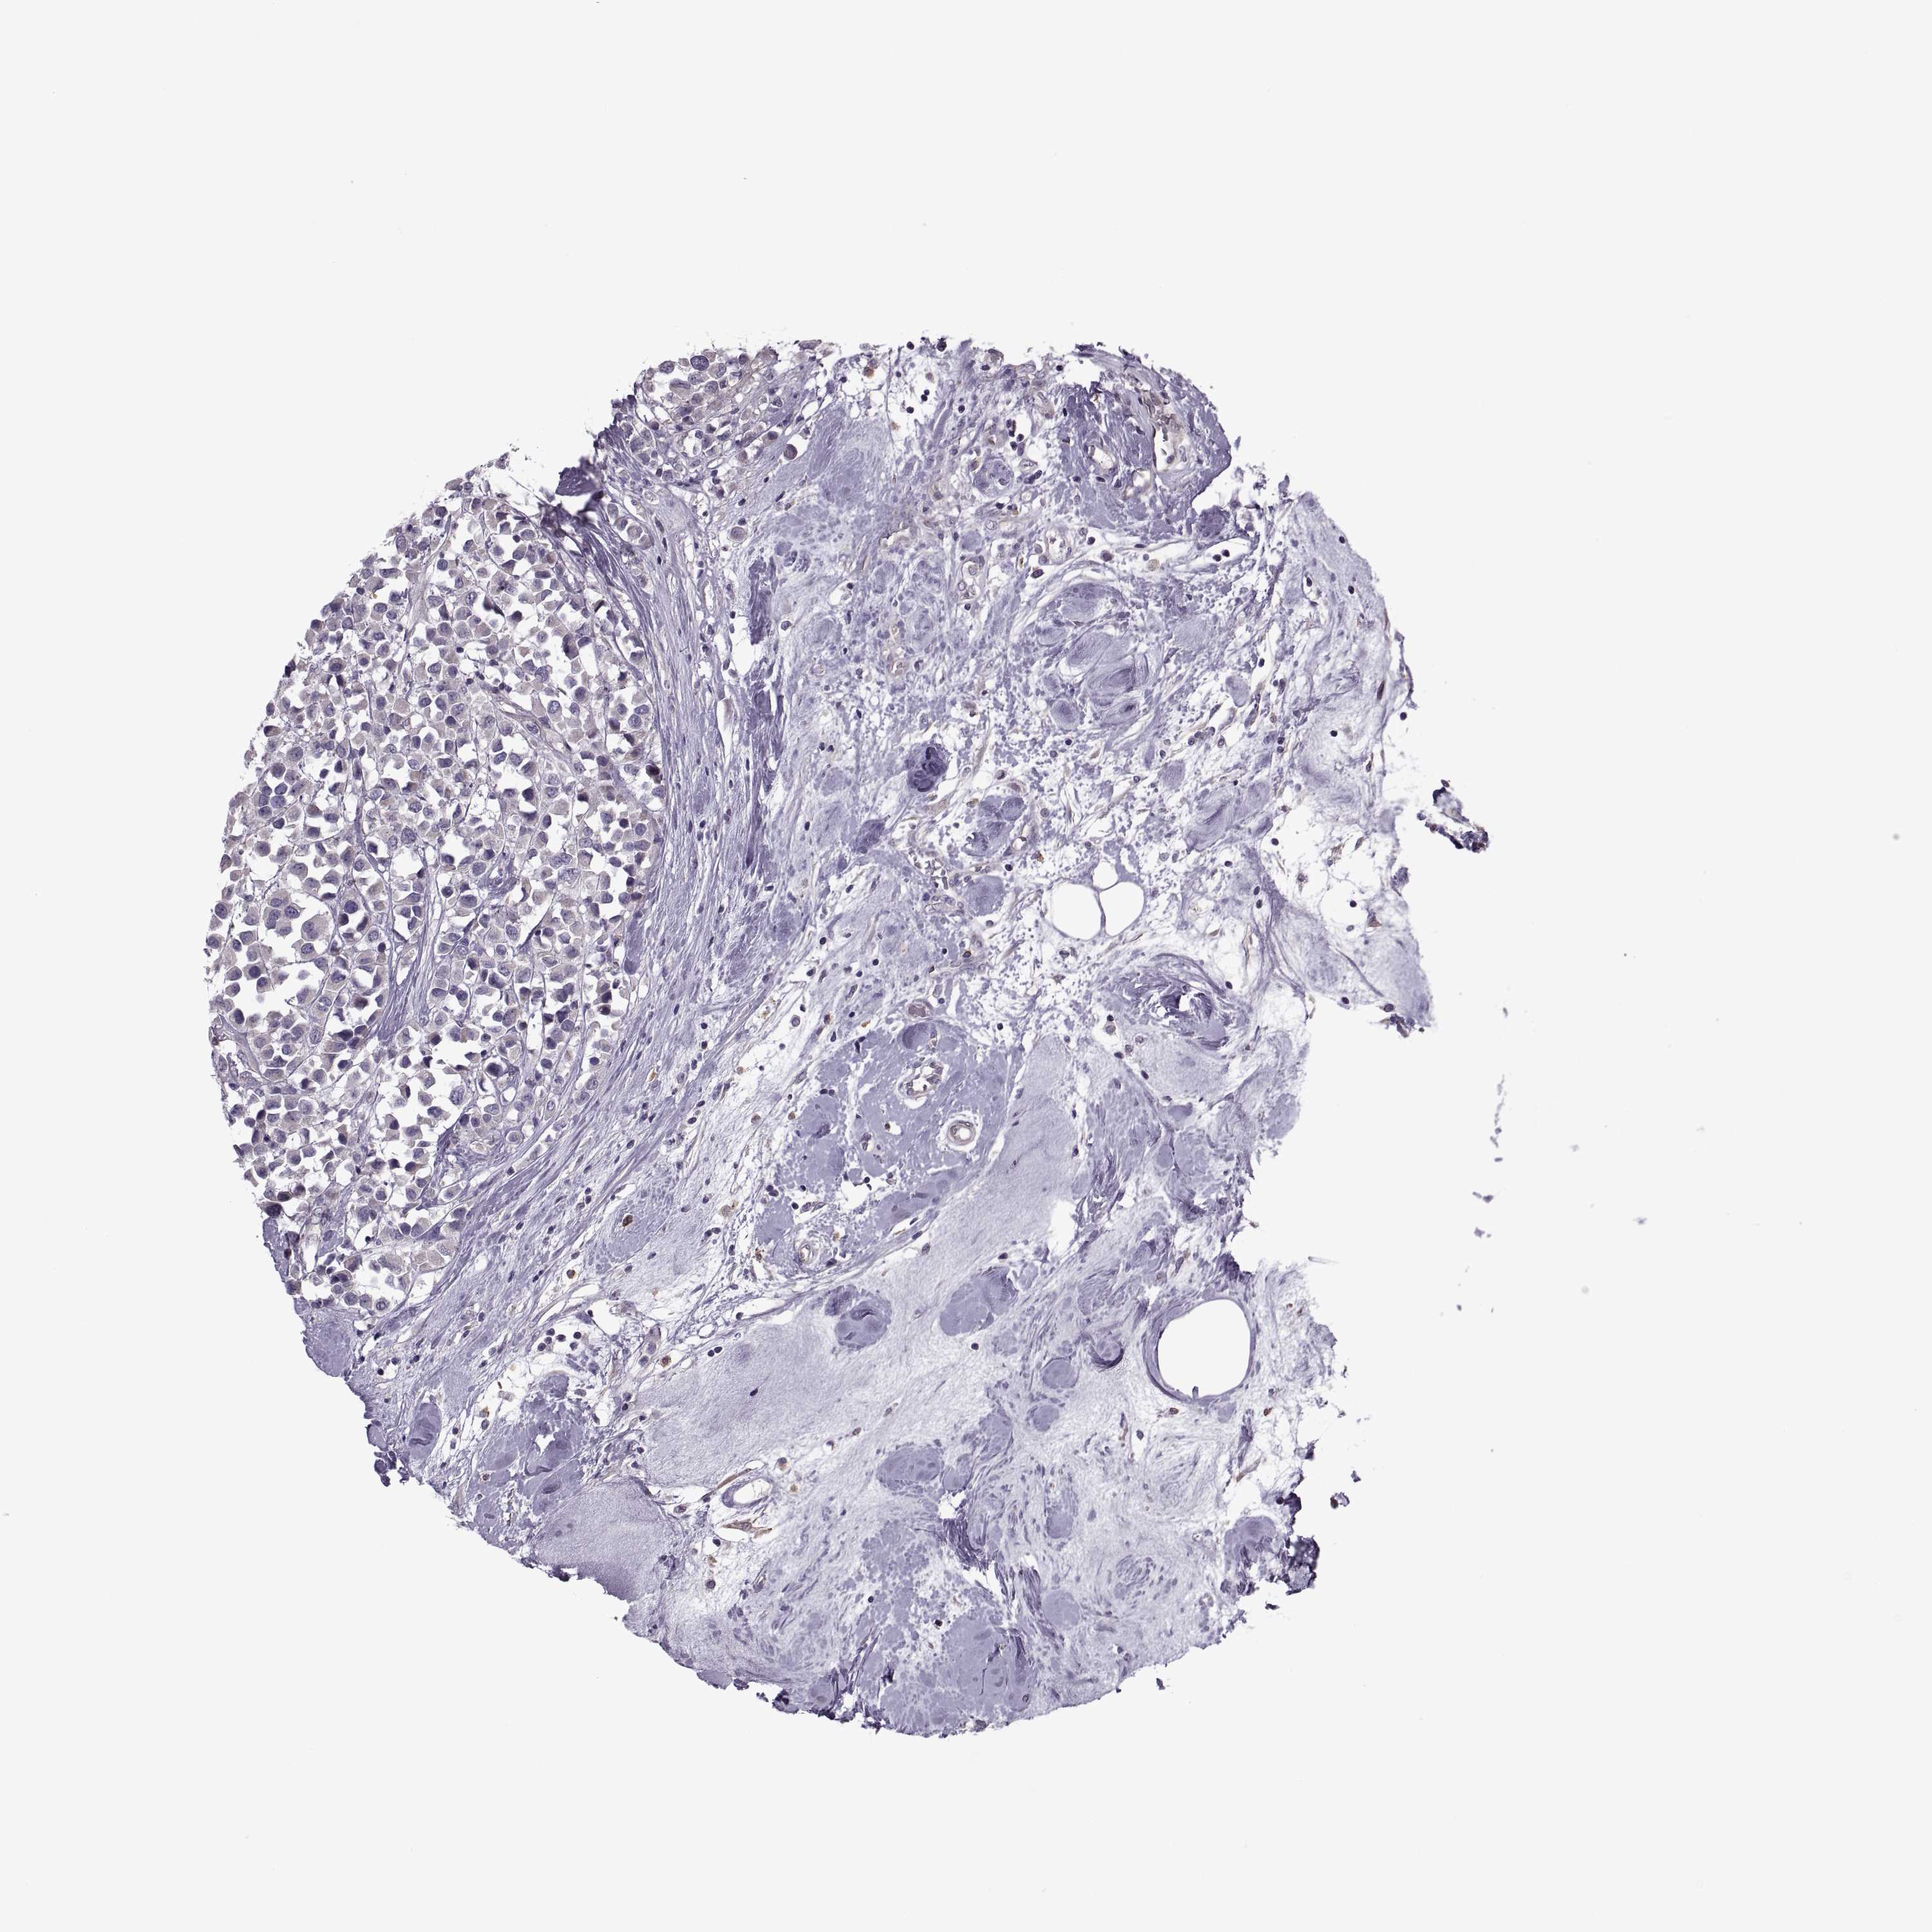

CANCER BREAST CANCER Show tissue menu

BRCA TCGA BRCA VALIDATION PROTEIN EXPRESSION

Breast cancer

Human cancer